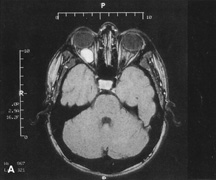

Magnetic resonance imaging is useful in selected cases, especially when evaluating the orbital cranial junction. Significant bony artifact and a lack of orbital fat in the orbital apex make CT scan resolution of the orbital apex structures poor. Because cortical bone has low signal on MRI, there is no bone artifact when viewing the orbital apex on MRI. The lack of intervening fat in the apex to provide contrast is overcome on MRI because contrast is provided by the individual nuclear characteristics of each tissue so that the orbital apex structures are visualized well. Consequently, conditions that affect the optic nerve and chiasm, such as optic nerve meningioma and glioma, generally are evaluated with MRI rather than CT scan (Fig. 2).

Fig. 2. A. Axial orbital CT scan of right optic nerve meningioma. Note lack of detail in orbital apex. B. Axial orbital MR image, same patient. Note increased detail in orbital apex owing to lack of bone artifact. C. MRI with gadolinium contrast. Note extension into brain not easily appreciated with CT scanning or MRI without contrast.